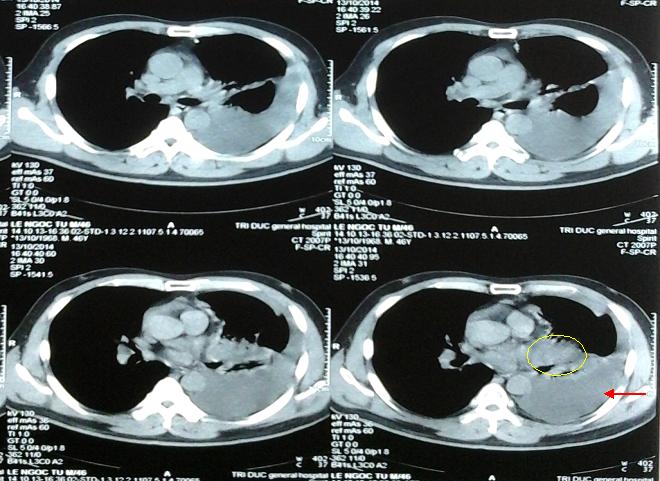

Hình 2. Hình ảnh chụp cắt lớp vi tính ngày 13/10/2014, khối u kích thước 4x4cm (vòng tròn vàng), tràn dịch màng phổi trái (mũi tên)